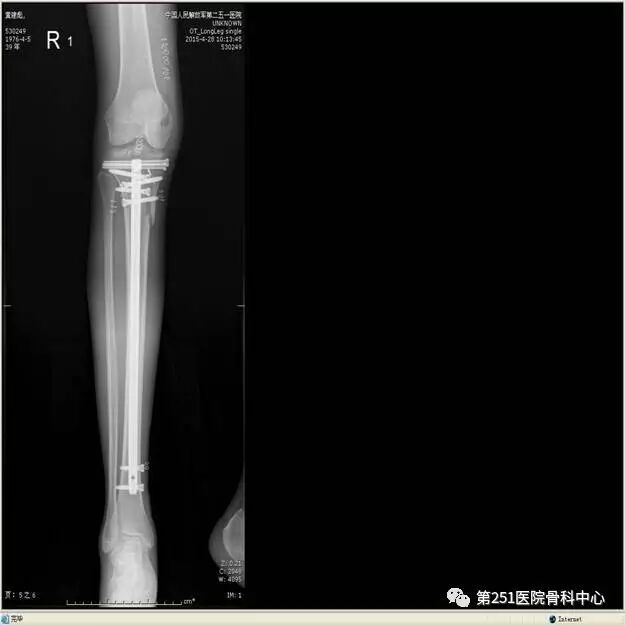

病例1:男性,40岁,车祸伤,胫腓骨多段骨折。